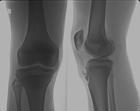

就诊科室:内科 风湿免疫科易感人群:无特殊人群需做检查:血常规 便常规 免疫病理检查 四肢的骨和关节平片 骨关节及软组织CT检查 骨与关节MRI检查 关节腔液检查 抗类风湿性关节炎33抗体常用药物:小儿复方四维亚铁散 龙牡壮骨颗粒 阿法骨化醇软胶囊 小儿四维葡钙颗粒 醋酸钙颗粒 阿法骨化醇片 维B1乳酸钙片 碳酸钙颗粒 三维鱼肝油乳 氯化钙溴化钠注射液 磷酸氢钙片 阿法骨化醇胶囊 氯芬待因片 牡蛎碳酸钙颗粒典型症状:耳廓痛 咽鼓管堵塞 鞍鼻 抽搐 传导性耳聋 蛋白尿 巩膜外层炎传染方式:无传染性治疗方式:无传染性相关疾病:复发性多软骨炎性巩膜炎 剥脱性骨软骨炎 梅毒性骨软骨炎 复发性多发性软骨炎伴发的葡萄膜炎